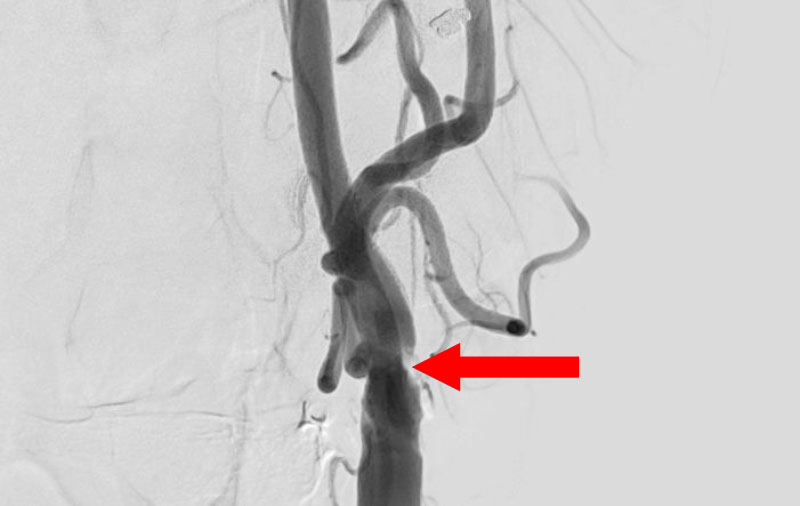

くも膜下出血

左中大脳動脈瘤破裂

40代

救急外来

No.1596 手術前